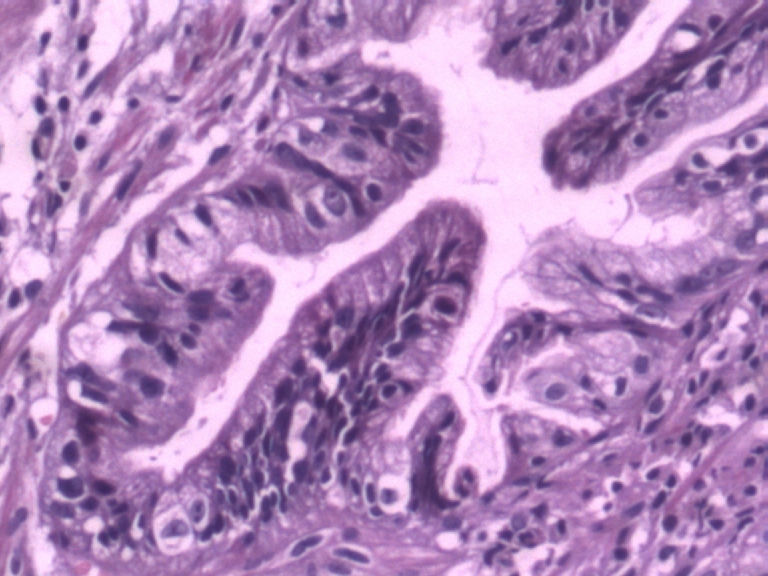

男,50岁,胃镜活检食管下段溃疡组织3块。

• 胃镜活检食管下段溃疡组织3块图3

图3

2图、3、4图上似乎有核分裂.可视为不典型增生。

请教一下2图、3、4图上似乎有核分裂如何看待? 学习了!谢谢各位老师!

倾向良性,腺体形态的改变符合炎症修复所致。

胃镜取材部位距门齿多少厘米?没有看到鳞状上皮,是贲门或者胃食管交界处吧?

结构很重要,请给几张低倍图。从现有的图看不够癌。